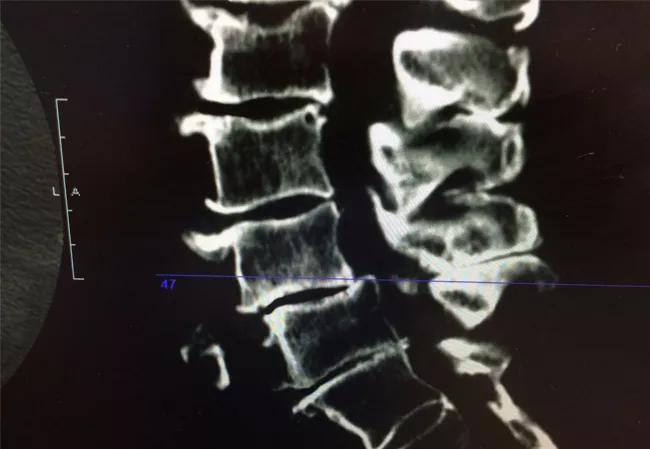

Patients with moderate to severe lumbar spinal stenosis (LSS) often can’t stand longer than a few minutes or walk more than a few hundred feet without developing severe pain. This significantly impacts their quality of life. Until a few years ago, the only treatment options available for patients with LSS were conservative therapies or open spine surgery.

LSS may be due to a bulging disk and/or hypertrophy of the ligamentum flavum. Narrowing of the spinal canal causes nerve compression. When someone with LSS stands or walks, the spinal canal narrows even more, causing low back and leg pain that is relieved with sitting or bending forward, which is called neurogenic claudication.

Patients with moderate to severe LSS may be candidates for mild if they complain of neurogenic claudication and if the MRI shows that ligamentum flavum hypertrophy is the major cause of the spinal stenosis, Dr. Mekhail explains.

The mild procedure is performed under deep sedation through a 1-cm incision. The clinician uses a special sculpting tool that glides through a portal with a diameter of 5 mm, about the size of a pen cap, to go between the bones, scrape out the ligament and widen the spinal canal to reduce nerve roots compression. Contrast material is injected into the epidural space to assess positioning and guide with visualization throughout the procedure.